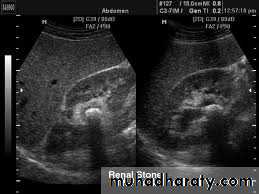

Ultrasound findings

1-Dilatation of the P.C.S. appears as multilocular fluid collection within central echo complex.-With more severe distention, dilated calyces appear as

Multiple cysts but communicating with each other unlike true cysts.

2-Stones larger than 5mm are easily seen on US but smaller ones may be missed.

-They produce intense echoes (hyperechoic) and cast acoustic shadows.